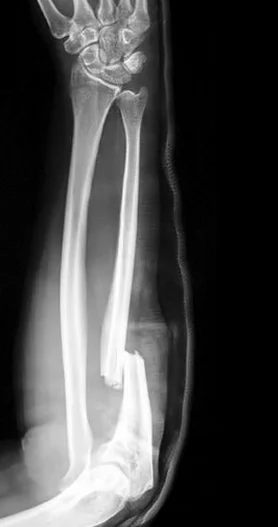

Monteggia Fracture/Dislocation

- Fracture of the proximal third of the ulna with dislocation of the head of the radius

- Dislocated head of radius missed if two joints are not included on the x-ray

- “Fracture of necessity”. Treated by:

- Open reduction and internal fixation of ulna

- Closed reduction of head of radius

- +/- fixation